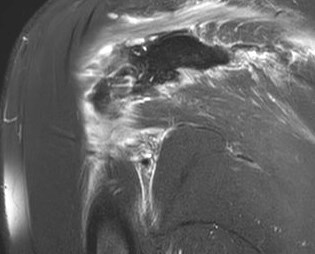

Figure 4 for case Stab wound

Figure 4

Discussion

Filled with hemorrhage. The infraspinatus took the brunt.